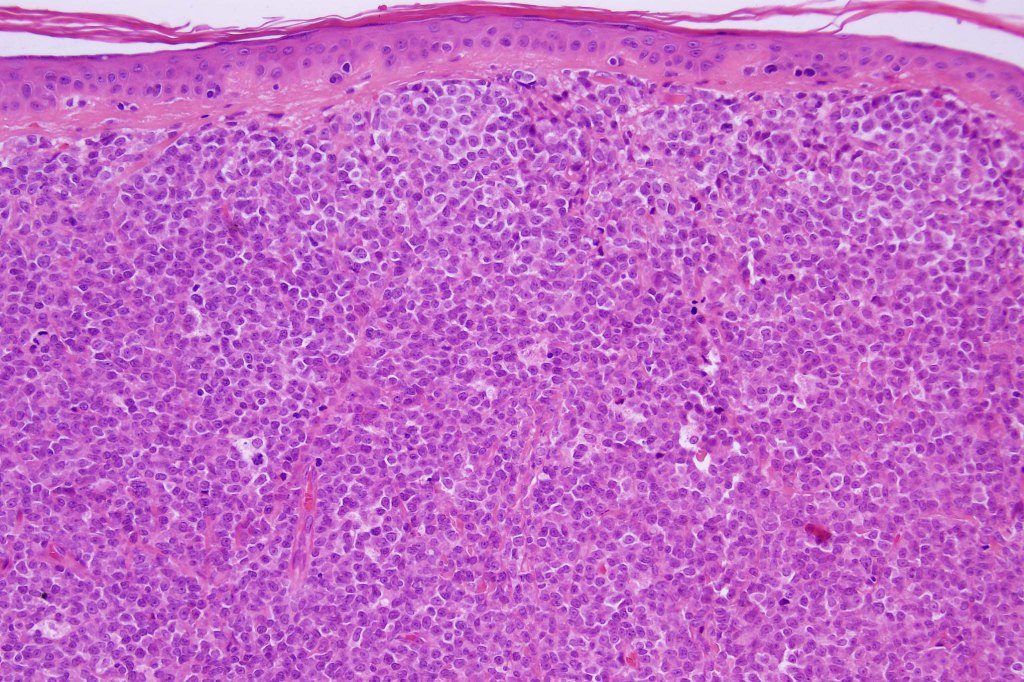

Histological features

. No epidermal involvement

. Dermal +/- subcutaneous fat infiltrate

. Monotonous blast cells with gray-blue cytoplasm & irrregular vesicular nuclei with prominent nucleoli